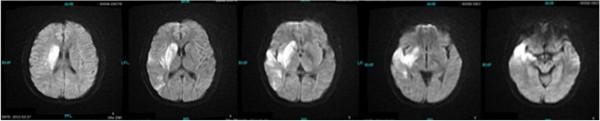

A 35-year-old Chinese woman presented to the Emergency Department with left hemiparesis, pain and numbness of her arms and weak radial pulses. Her laboratory results showed an elevated C-reactive protein and erythrocyte sedimentation rate, and subsequent digital subtraction angiography demonstrated narrowing and occlusion of the major branches of her aortic arch. We report the case of a patient with Takayasu arteritis presenting with a massive cerebral ischemic infarct and review the current literature on this topic.

一名35岁的中国女性因左侧偏瘫、手臂疼痛和麻木以及桡动脉搏动减弱就诊于急诊科。她的实验室检查结果显示C反应蛋白和红细胞沉降率升高,随后的数字减影血管造影显示其主动脉弓主要分支狭窄和闭塞。我们报告一例患有高安动脉炎并出现大面积脑缺血梗死的患者病例,并回顾关于该主题的当前文献。